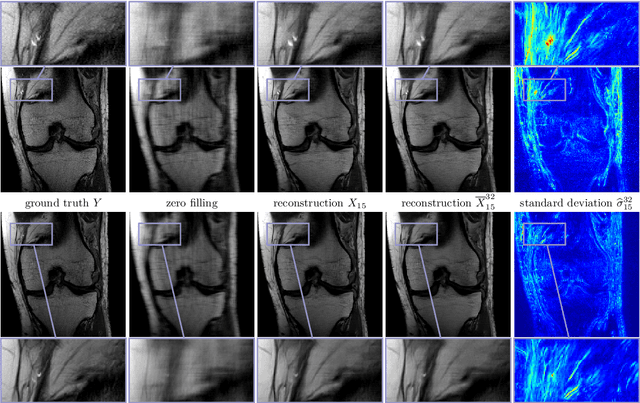

Abstract:Recent deep learning approaches focus on improving quantitative scores of dedicated benchmarks, and therefore only reduce the observation-related (aleatoric) uncertainty. However, the model-immanent (epistemic) uncertainty is less frequently systematically analyzed. In this work, we introduce a Bayesian variational framework to quantify the epistemic uncertainty. To this end, we solve the linear inverse problem of undersampled MRI reconstruction in a variational setting. The associated energy functional is composed of a data fidelity term and the total deep variation (TDV) as a learned parametric regularizer. To estimate the epistemic uncertainty we draw the parameters of the TDV regularizer from a multivariate Gaussian distribution, whose mean and covariance matrix are learned in a stochastic optimal control problem. In several numerical experiments, we demonstrate that our approach yields competitive results for undersampled MRI reconstruction. Moreover, we can accurately quantify the pixelwise epistemic uncertainty, which can serve radiologists as an additional resource to visualize reconstruction reliability.